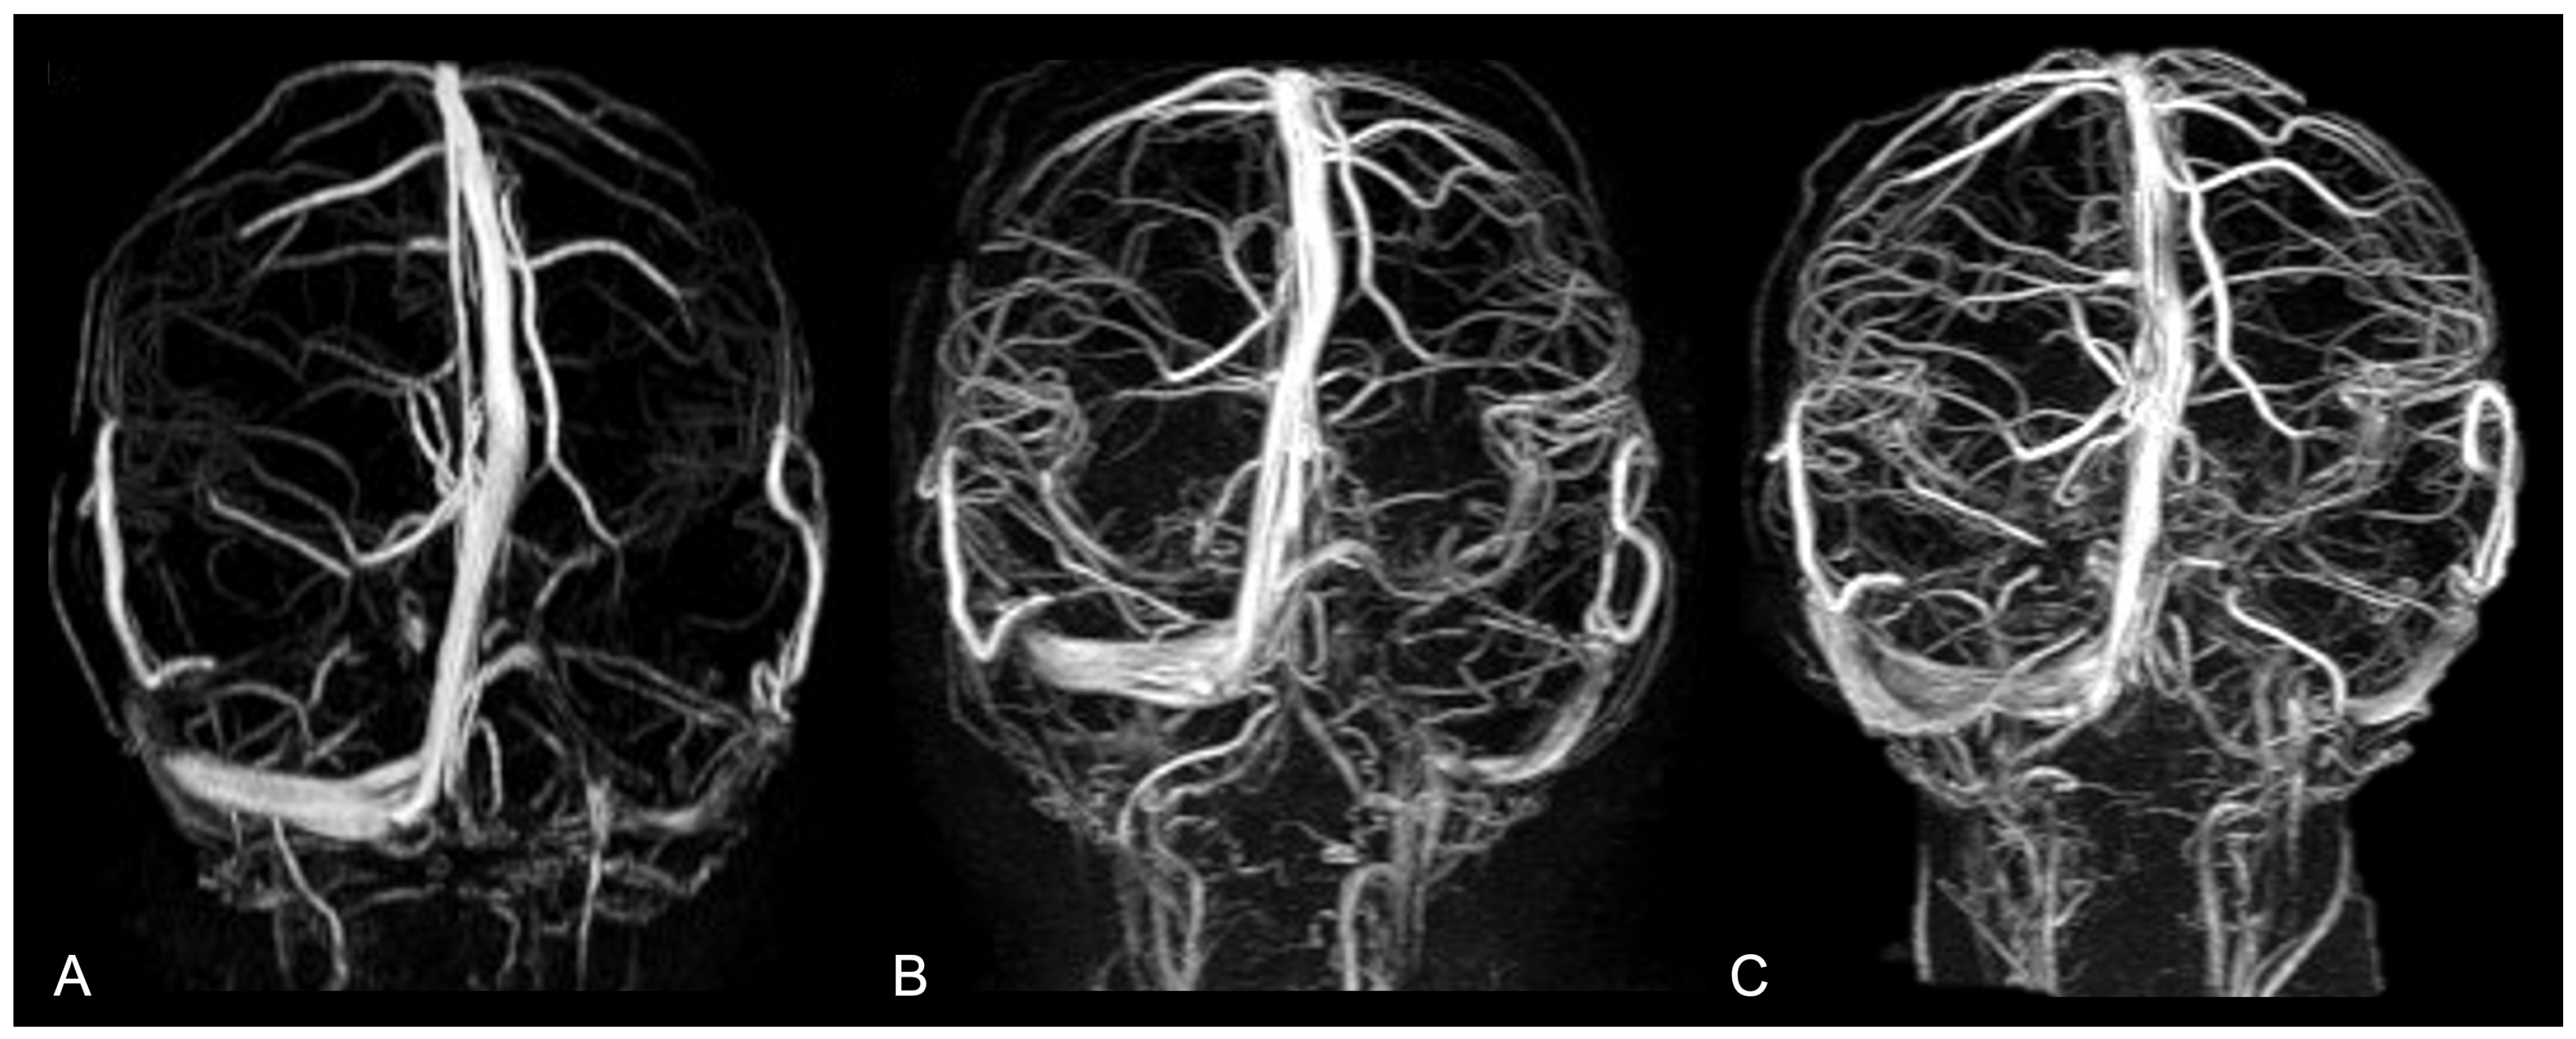

- de Planque, C.A.; Mutsaerts, H.J.M.M.; Keil, V.C.; Erler, N.S.; Dremmen, M.H.G.; Mathijssen, I.M.J.; Petr, J. Using Perfusion Contrast for Spatial Normalization of ASL MRI Images in a Pediatric Craniosynostosis Population. Front. Neurosci. 2021, 15, 698007. [Google Scholar] [CrossRef]

- de Planque, C.A.; Petr, J.; Gaillard, L.; Mutsaerts, H.J.M.M.M.; van Veelen, M.-L.C.M.; Versnel, S.L.M.; Dremmen, M.H.G.; Mathijssen, I.M.J.M. Cerebral Blood Flow of the Frontal Lobe in Untreated Children with Trigonocephaly versus Healthy Controls: An Arterial Spin Labeling Study. Plast. Reconstr. Surg. 2022, 149, 931–937. [Google Scholar] [CrossRef]

- Doerga, P.N.; Lequin, M.H.; Dremmen, M.H.G.; Ottelander, B.K.D.; Mauff, K.A.L.; Wagner, M.W.; Hernandez-Tamames, J.A.; Versnel, S.L.; Joosten, K.F.M.; van Veelen, M.-L.C.; et al. Cerebral blood flow in children with syndromic craniosynostosis: Cohort arterial spin labeling studies. J. Neurosurg. Pediatr. Am. Assoc. Neurol. Surg. 2020, 25, 340–350. [Google Scholar] [CrossRef]

- Aslan, S.T.; Demïrcï, H. Investigation of the Effffect of Cranial Vault Surgery On Parenchymal Perfusion Before and After Surgery in Craniosynostosis Patients. Turk. J. Pediatr. Dis. 2023, 17, 160–165. [Google Scholar] [CrossRef]